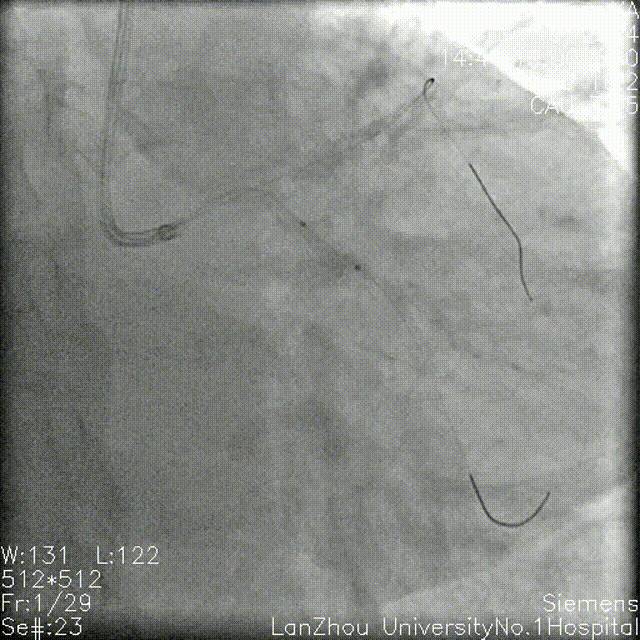

GC:7F EBU 3.5 前降支、回旋支分别植入导丝 1.5*15mm球囊 12atm分别预处理回旋支开口、近端,血流恢复TIMI III级。

2.0*20mm球囊 再次扩张,造影血管显影更清晰。

2.0*15mm双导丝球囊 14atm修饰回旋支开口-左主干末端。

多次尝试推送2.5mm NC球囊,仍无法通过前降支近端,遂决定行旋磨术。

1.5mm旋磨,15万转3次共48s旋磨、修饰前降支近-中段。

2.5*12mm、 3.0*12mmNS 球囊高压扩张前降支。

2.5*12mm、 3.0*12mmNC 球囊高压扩张前降支,复查造影提示狭窄明显减轻。

2.75*28mm支架 8atm于前降支近中段释放,复查造影狭窄解除。

复查造影提示回旋支开口仍明显狭窄,考虑使用药球后可能回弹,遂决定行支架植入,于回旋支近端-左主干行Cullotte术,2.75*18mm 10atm释放支架。

前降支Re-wire,1.5mm、2.0 mm、2.5mm球囊扩张回旋支-左主干支架网眼。

与前降支近中段原支架串联前降支近端至左主干 12atm释放3.5*32mm支架。

回旋支Re-wire, 1.5mm、2.0 mm、2.5mm球囊扩张前降支-左主干支架网眼;

2.75*15mm,3.5*12mm球囊扩张前降支-左主干,2.75mm球囊扩张回旋支;

2.75mm,3.5mm 8atm対吻扩张。